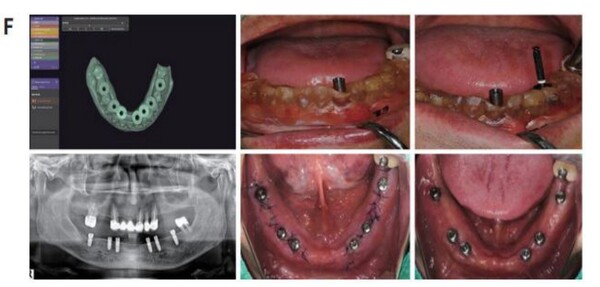

구강내 Scanning date Vertual wax-up date CT data를 융합하여 임플란트의 식립 위치, 방향을 결정하고 SurgiG uide를 제작하였다. SurgiGuide를 이용하여 임플란트를 식립하였으며, 1 주일 후에 stitch out 한 후 임시보철물을 위해 fixture에 scan body를 연결하고 seaming하여 PMMA 임시보철불을 제작하여 구강내에 장착하여 주었다.